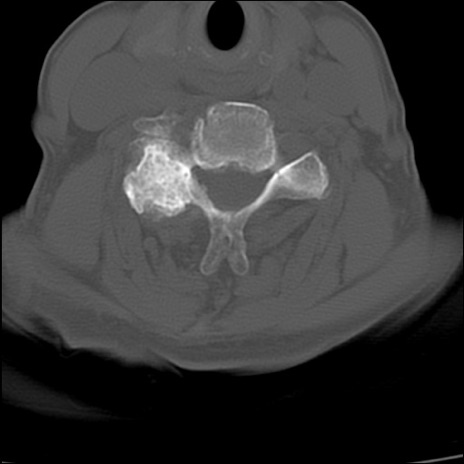

症例48 頚椎CT(横断像)

頚椎CT